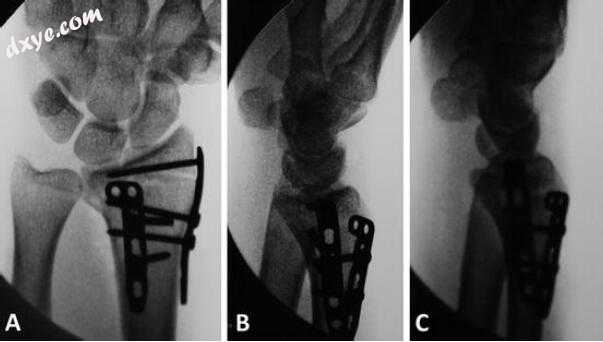

图7.8术中采集的最终PA(a),侧(b)和斜(c)透视图,以确认解剖复位

然后在术后2周在诊所看到患者,在那里她的夹板和缝合线被移除,并且她开始了数字/手腕/前臂ROM的监督治疗程序。 然后在术后6周,10周和6个月在临床上观察患者(图7.9和7.10)。 患者在屈曲,伸展,旋后和旋前的运动范围与对侧相同。 在术后9个月,她接受了硬件的选择性切除。